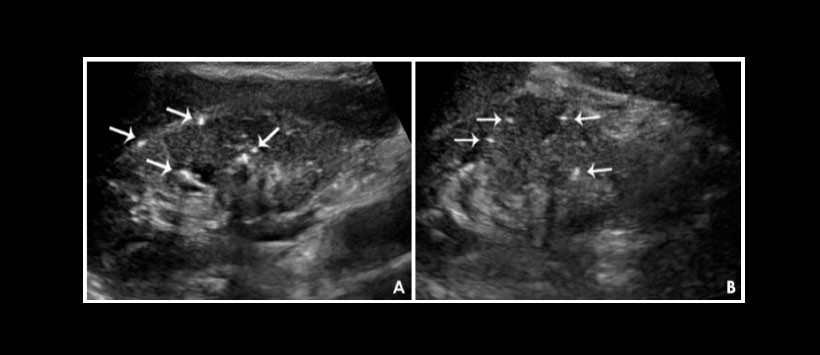

Como este tipo de amelogénesis imperfecta puede asociarse con otras anormalidades metabólicas y de órganos, se llevaron a cabo investigaciones adicionales. Un examen de ultrasonido de sus riñones mostró múltiples focos hiperecoicos en la médula de ambos riñones, lo que sugiere una nefrolitiasis bilateral (Figuras 4A y B). Un análisis espectrofotométrico de orina de 24 horas reveló niveles muy bajos de citrato.